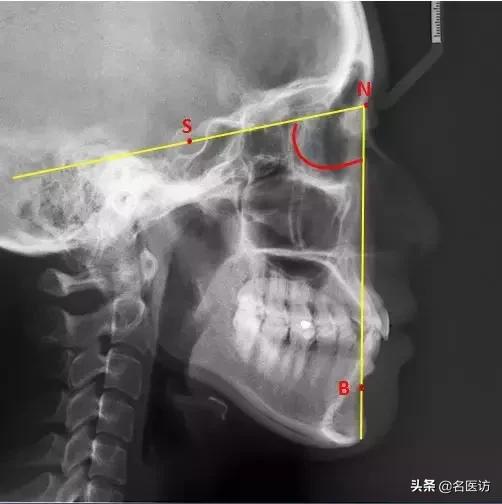

2、评估下颌位置:SNB角

B:下牙槽座点,下牙槽和颏部接触的最凹点

当该角过大时下颌相对前颅底的位置前突;反之呈颌后缩。